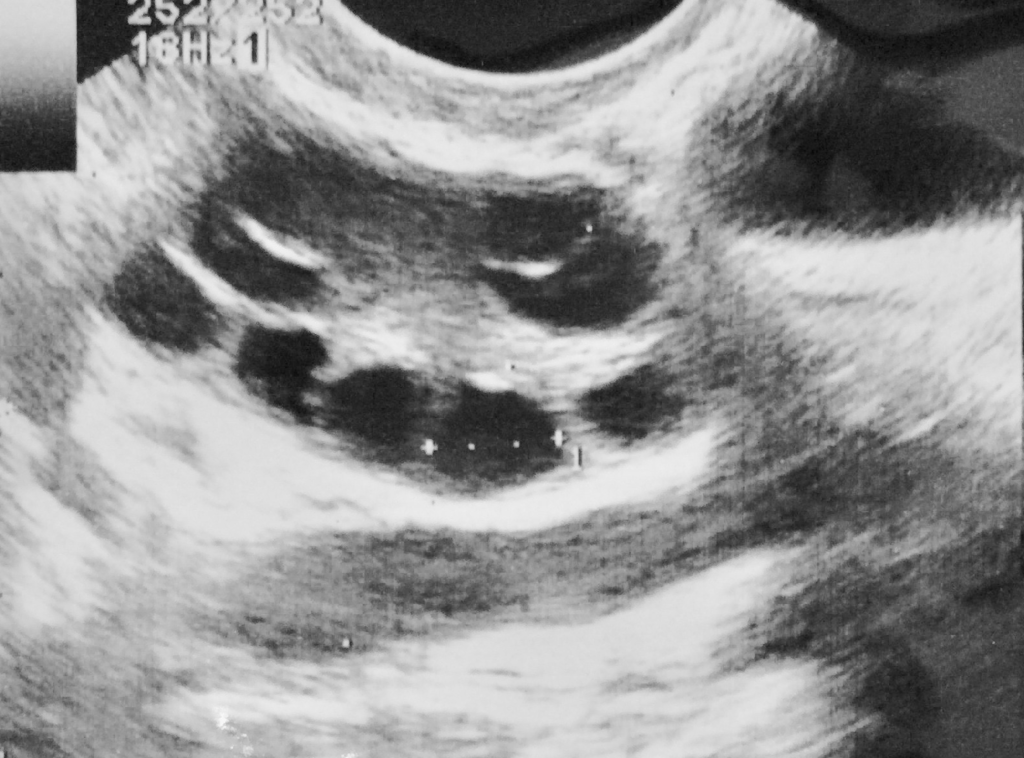

出産適齢期の女性では、卵胞として知られる小さな液体で満たされた嚢胞が毎月、卵巣の表面に発生します。 エストロゲンを含む女性ホルモンは、卵胞の 1 つに成熟した卵子を生成させます。その後、卵巣はこの卵子を放出し、卵胞から飛び出します。

- 卵巣嚢腫

- 超音波スキャン